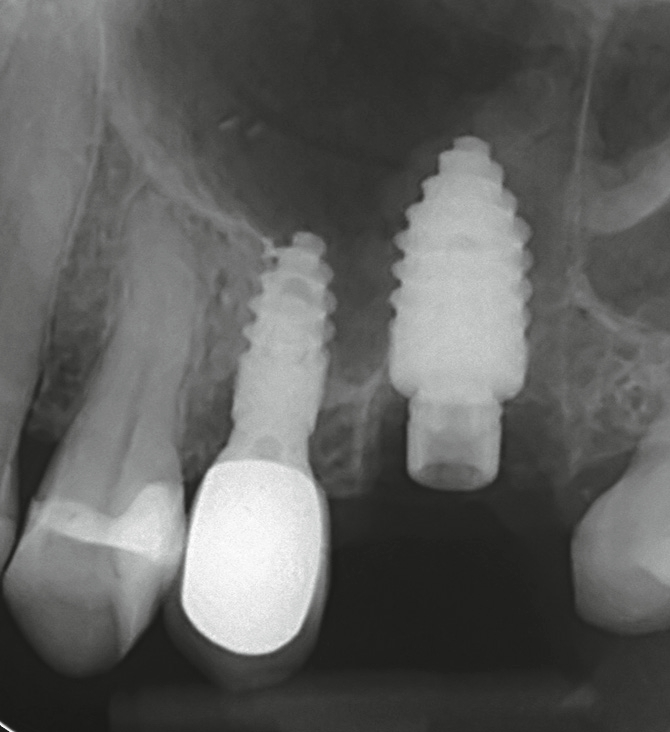

Widerwillig reifte in mir der unschöne Gedanke an einen Längsriss der palatinalen Wurzel des Zahnes 26. Die Beschwerden und der unauffällige Röntgenbefund ließen nur diese Diagnose schlüssig erscheinen. Ich wandte mich bezüglich einer erneuten Behandlung an Dr. Armin Nedjat. Nach Infiltrationsanästhesie, mittels MagicPen, entfernte Dr. Nedjat die Goldkrone. Er extrahierte den dreiwurzeligen Zahn und versuchte, in den vorhandenen Alveolarknochen, welcher durch die Trifurkation eingeschlossen war, zu implantieren. Der erfahrene Behandler benutzte zunächst den gelben konischen Dreikantbohrer. Danach erfolgte im D3- Knochen die Verdichtung des Knochens mit dem Ziel, eine Primärstabilität von 30–40 Ncm mit den Kondensern vom Durchmesser 2,4 mm, 3,0 mm, 3,8 mm, 4,3 mm zu erreichen. Nach dem Kondenser mit Durchmesser 5,3 mm war erst eine ausreichende Stabilität von 35 Ncm erzielt worden (Abb. 2). Minimalinvasiv wurde ein direkter Sinuslift durchgeführt – genial einfach durch Linkslauf des orangen Krestalbohrers vom Durchmesser 3,7 mm. Auf diese Weise kann die Schneider- Membran um bis zu 10 (!) mm angehoben werden. Ein Champions® (R)Evolution Titan-Implantat, Durchmesser 5,5 mm, Länge 10 mm, wurde inseriert (Abb. 3).

Nachdem der Behandler sämtliche Füllungs-, Wurzelfüllmaterialien sowie Zementreste von seiner Assistenz entfernen ließ, wurden die Zahnfragmente im Luftstrom der Multifunktionsspritze getrocknet und in den Champions Smart Grinder gegeben (Abb. 4). Nach wenigen Sekunden später war der Zahn zerkleinert. Es folgte eine 10-minütige Entkeimung und eine 3-minütige Neutralisation und das Augmentat war einsatzbereit. Es ließ sich sehr gut adaptieren, da es am Spatel leicht anhaftete. Autologer Dentingraft induziert nun Knochenwachstum (Abb. 5).

Glücklich verließ ich den Behandlungsstuhl, wohlwissend, welche Behandlung konventioneller Implantation mit externem Sinuslift und Einheilzeiten von bis zu einem Jahr mir erspart geblieben war. Seither bin ich begeisterter Anwender des Champions Smart Grinders. Die Abbildung 6 zeigt die Situation nach 12 Wochen.